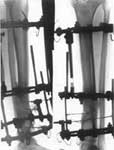

2.Остеосинтез с устранением деформаций и электростимуляции остеорекарации(срок лечения - 3 месяца )